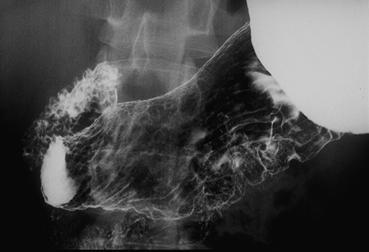

IIc型早期胃癌のX線像    背臥位による胃二重造影写真です。胃角部の小弯から後壁にかけて、粘膜の不整が認められます。

疾患(病理主体)の分類悪性上皮性腫瘍/印環細胞癌

部位(臓器別)胃(部位)/胃角

検査方法X-P

腫瘍の肉眼分類0型(表在型)/IIc型(IIc)

病変の最大径(ミリ)30〜34

腫瘍の深達度m